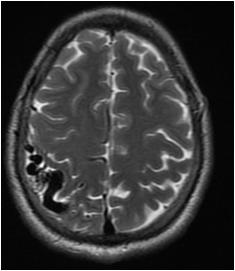

Fig 1 — CT Imaging from a patient of Basal Ganglia hemorrhage in the present study